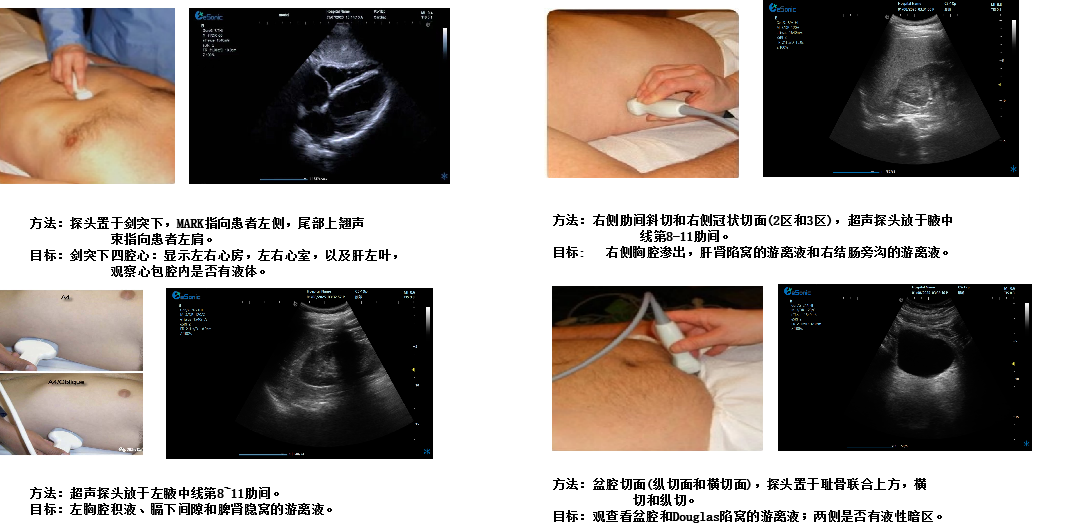

重症心脏超声- FATE方案:

是重症病人循环管理推荐的目标导向超声评估评估方案之一,在此基础上扩展快速的下腔静脉超声检查,增加和完善容量状态和液体反应性的评估。

剑突下四腔心切面

image.png

扫查方法:探头置于剑突下,声束指向左肩,稍向上倾斜30°,接近心脏冠状切面

超声声像图:图像近场扇尖处可见肝实质反射,此切面可观察左心房、左心室、右心房、右心室、房间隔、室间隔、二尖瓣、三尖瓣等结构。

创伤评估FAST